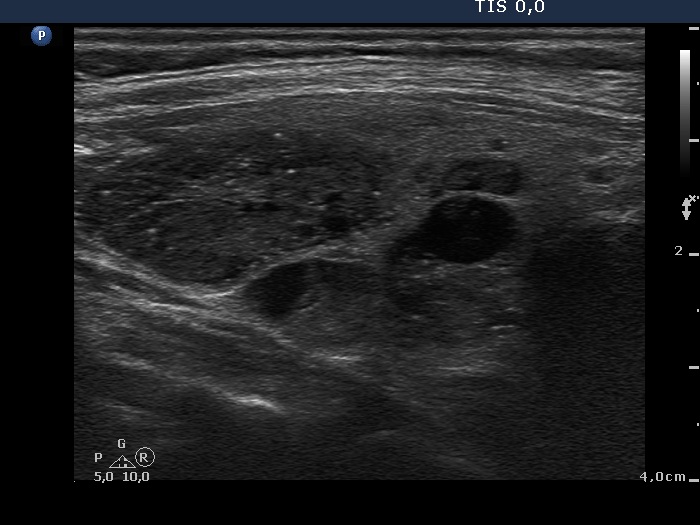

Benign hyperplastic nodule (histological diagnosis) - case cons039

|

Two foci of coarse calcification are presented, one in the left horizontal and another one in the right longitudinal scan.